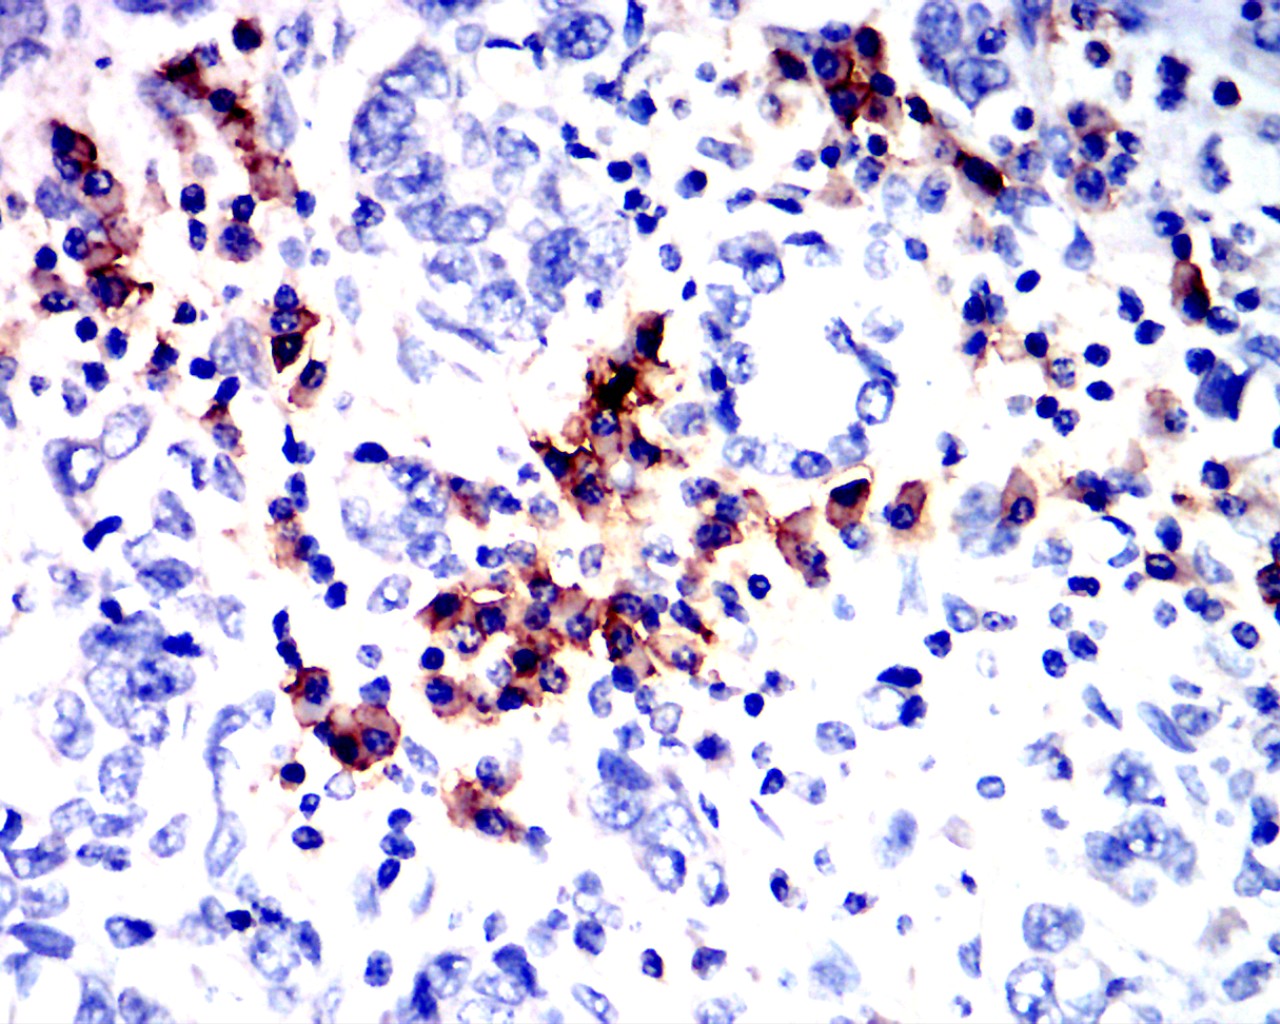

分类: 科研抗体货号: 90007别名: OMR; ORM; ATPM; MOM2; ATP5A; hATP1; ATP5A1; MC5DN4; ATP5AL2; COXPD22; HEL-S-123m应用: FCM反应种属: Human